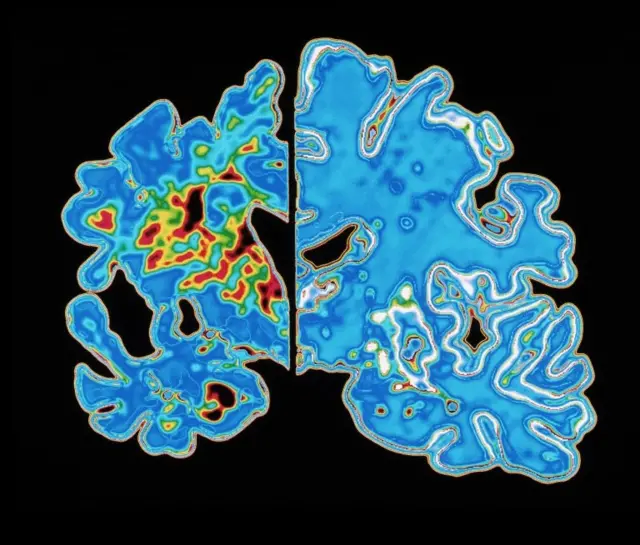

Sumber gambar, SCIENCE PHOTO LIBRARY